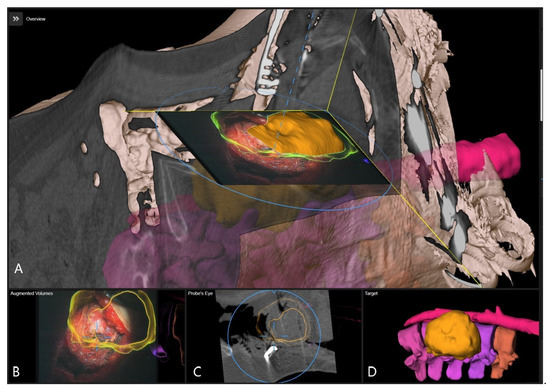

| 9 | L-Spine 70% | 13.80420 | 221.00 | 127.95180 | 168.00 | 141.76 | 2.81 | tumor, T12,L1, L2, L3, L4, kidney, vessels |

| 11 | T-Spine 70% | 19.82 | 144.00 | 145.00 | 117.00 | 164.82 | 3.10 | L3, L4, nerve root |

| 12 | T-Spine 70% | 24.74 | 190 | 201.82 | 164 | 226.56000 | 4.03 | Vertebral body T10, T11, T12, L1, L2, implant, clamp |